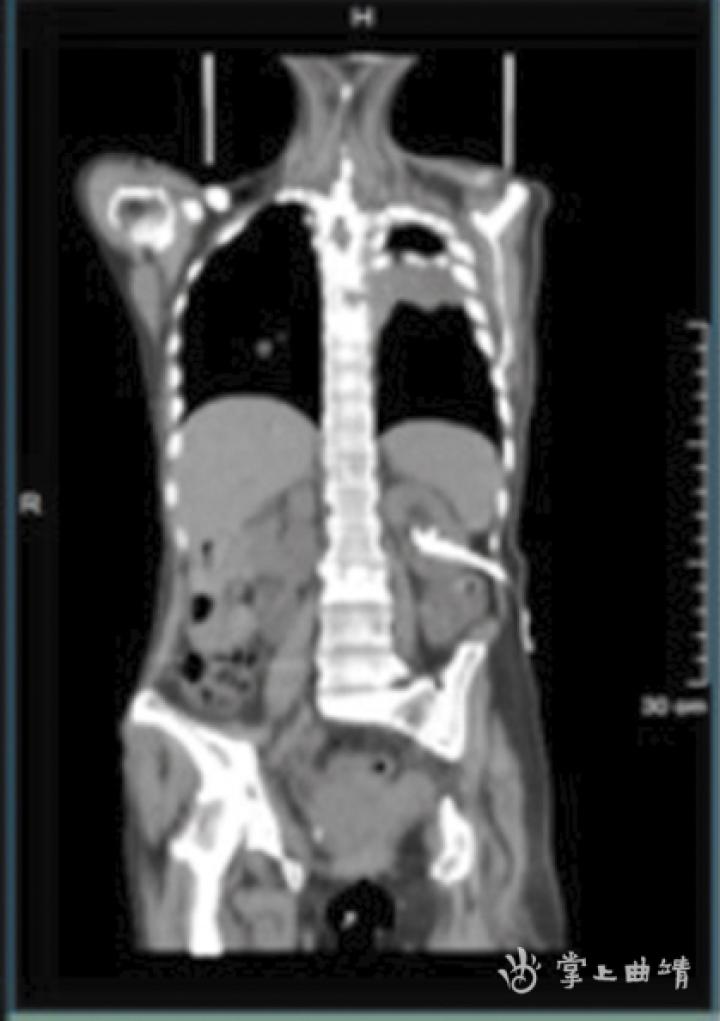

通过CT快速扫描显示解剖结构成像为后续PET图像提供衰减校正,为图像融合提供解剖结构基础。

PET显示的是病灶,而CT则清晰地显示病灶在哪个位置上,两者有机结合,既可以一眼看出人体的各个部位是否有异常,从而达到早期诊断的目的。

PET/CT检查前,需要注射正电子同位素标记的显像剂,其中主要的显像剂为18F-FDG,人称“世纪分子”,是一种放射性核素标记的脱氧葡萄糖。通过静脉注入微量18F-FDG后,发射的正电子与邻近组织的负电子发生作用,产生一对伽马光子。PET/CT扫描探头探测到伽马光子信号,并将信号传输给计算机处理,信号通过计算机处理显示出可视图像。从图像上可以清晰地看到病变处会有“发光”迹象,那是由于聚集的病变细胞不断吞噬、代谢注射到体内的18F-FDG,从而准确判断出病变的性质及部位。然后采用相应的治疗和康复手段,从而达到早发现、早诊断、早治疗、早康复的目的。